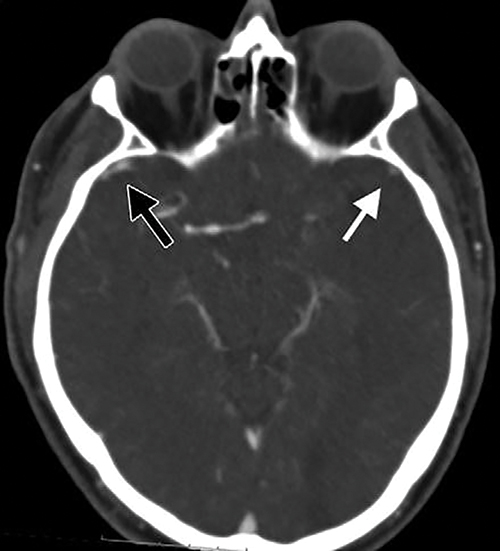

Image from a baseline CT angiography in 61-year-old man

Image from a baseline CT angiography in 61-year-old man with left-sided occlusion. In the affected hemisphere, sphenoparietal sinus is moderately opacified, resulting in opacification grade of 1 (white arrow). In unaffected hemisphere, sphenopariatal sinus is fully opacified, with opacification grade of 2 (black arrow).